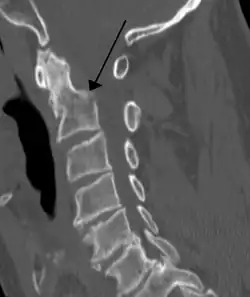

Sagittal reconstruction of a CT scan showing a cervical fracture with dislocation at the level of C6/7